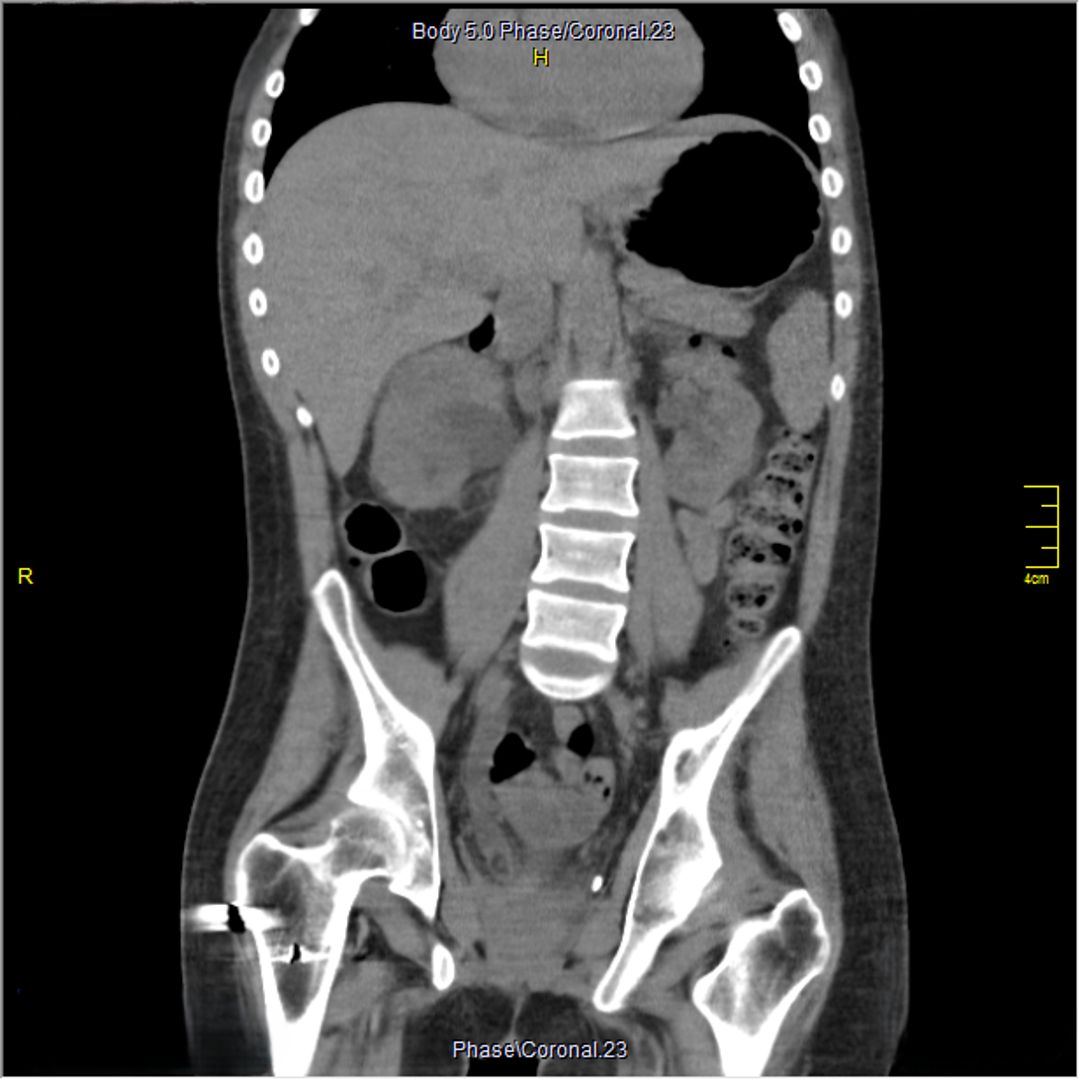

A 23-year-old male with a history of traumatic spinal cord injury (T3 ASIA A), iatrogenic urethral stenosis limiting clean intermittent catheterization (CIC), and low bladder capacity, was admitted for a planned open cystostomy and bladder stone extraction. Following stone removal, a 24-French SPC was placed. On postoperative day 3, the patient developed AD, characterized by hypertensive urgency and profuse sweating. Renal ultrasound revealed right-sided hydronephrosis. A CT scan confirmed SPC misplacement, with the catheter tip located inside the right distal ureter.

Figure 2 Coronal view of the SPC's tip in the distal right ureter provoking hydronephrosis

Figure 3 Axial view of the SPC's tip in the distal right ureter